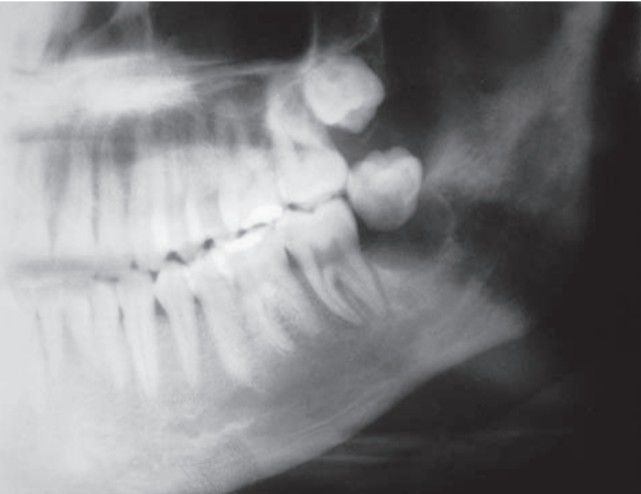

Postradiation chondrosarcoma

Swelling, pain, or paresthesia may be present; prognosis fair to poor, better if in mandible; often misdiagnosed as benign cartilage lesion.